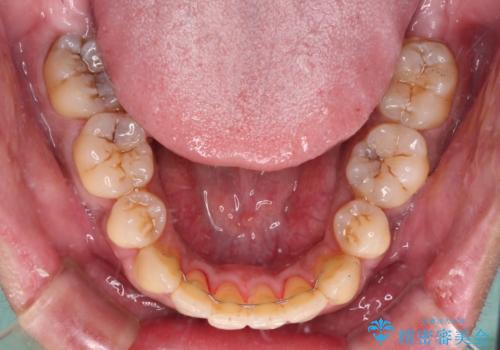

舌の突出癖を改善するためのトレーニングを指導していましたが、なかなか改善することができず、ワイヤー装置を外してからも上下前歯に隙間ができやすい状況でした。